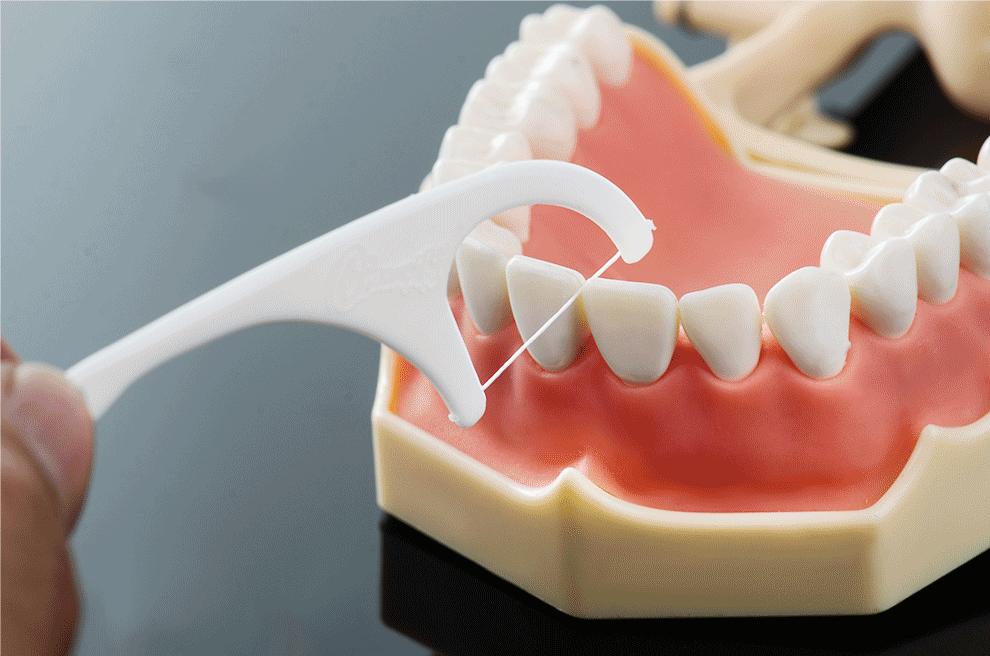

3、用牙线辅助清洁

光刷牙其实还不能深层清洁口腔,我们还可以适当使用牙线来辅助深层清洁牙齿,每天早晚或者吃完食物之后,用牙线刮掉牙缝里的残渣,再漱口。